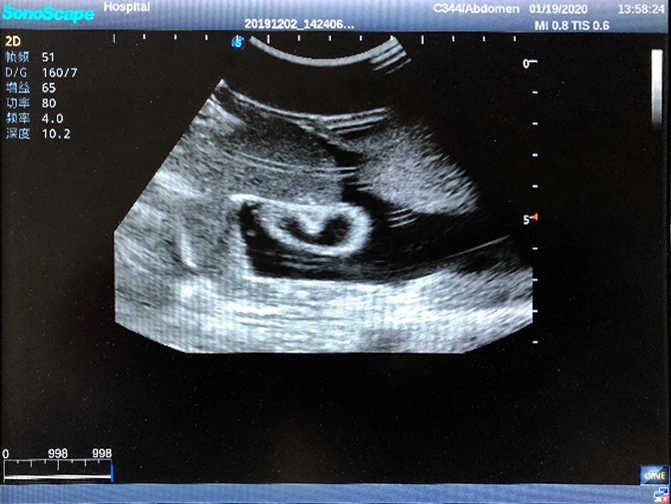

2) High quality ultrasound image with clear structures like gallbladder, liver, intestines, arteries and veins etc.

4) ltrasound gallbladder pathologies like cholecystitis, gallstone and polypoid degeneration

5) Normal & pathological ultrasound live and intestine models inside